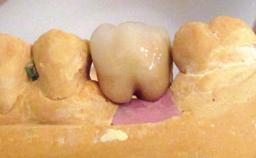

| Prosthesis Type | FDP |

| Retention | Cemented, with prosthesis margin < 3mm submucosal Cemented, with prosthesis margin < 3mm submucosal |

| Provisional Implant-Supported Prosthesis | Prosthodontic margin < 3 mm apical to mucosal crest Prosthodontic margin < 3 mm apical to mucosal crest |